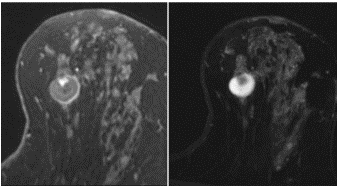

Inflamed cyst

MR: T2-hyperintense, oval or round mass; slow, persistent, uniformly thin rim (not nodular or irregular) enhancement

mucinous carcinoma/colloid carcinoma

-subtype of IDC

MR: Characteristic high-signal T2/STIR due to high mucin content; avid, slow rim enhancement